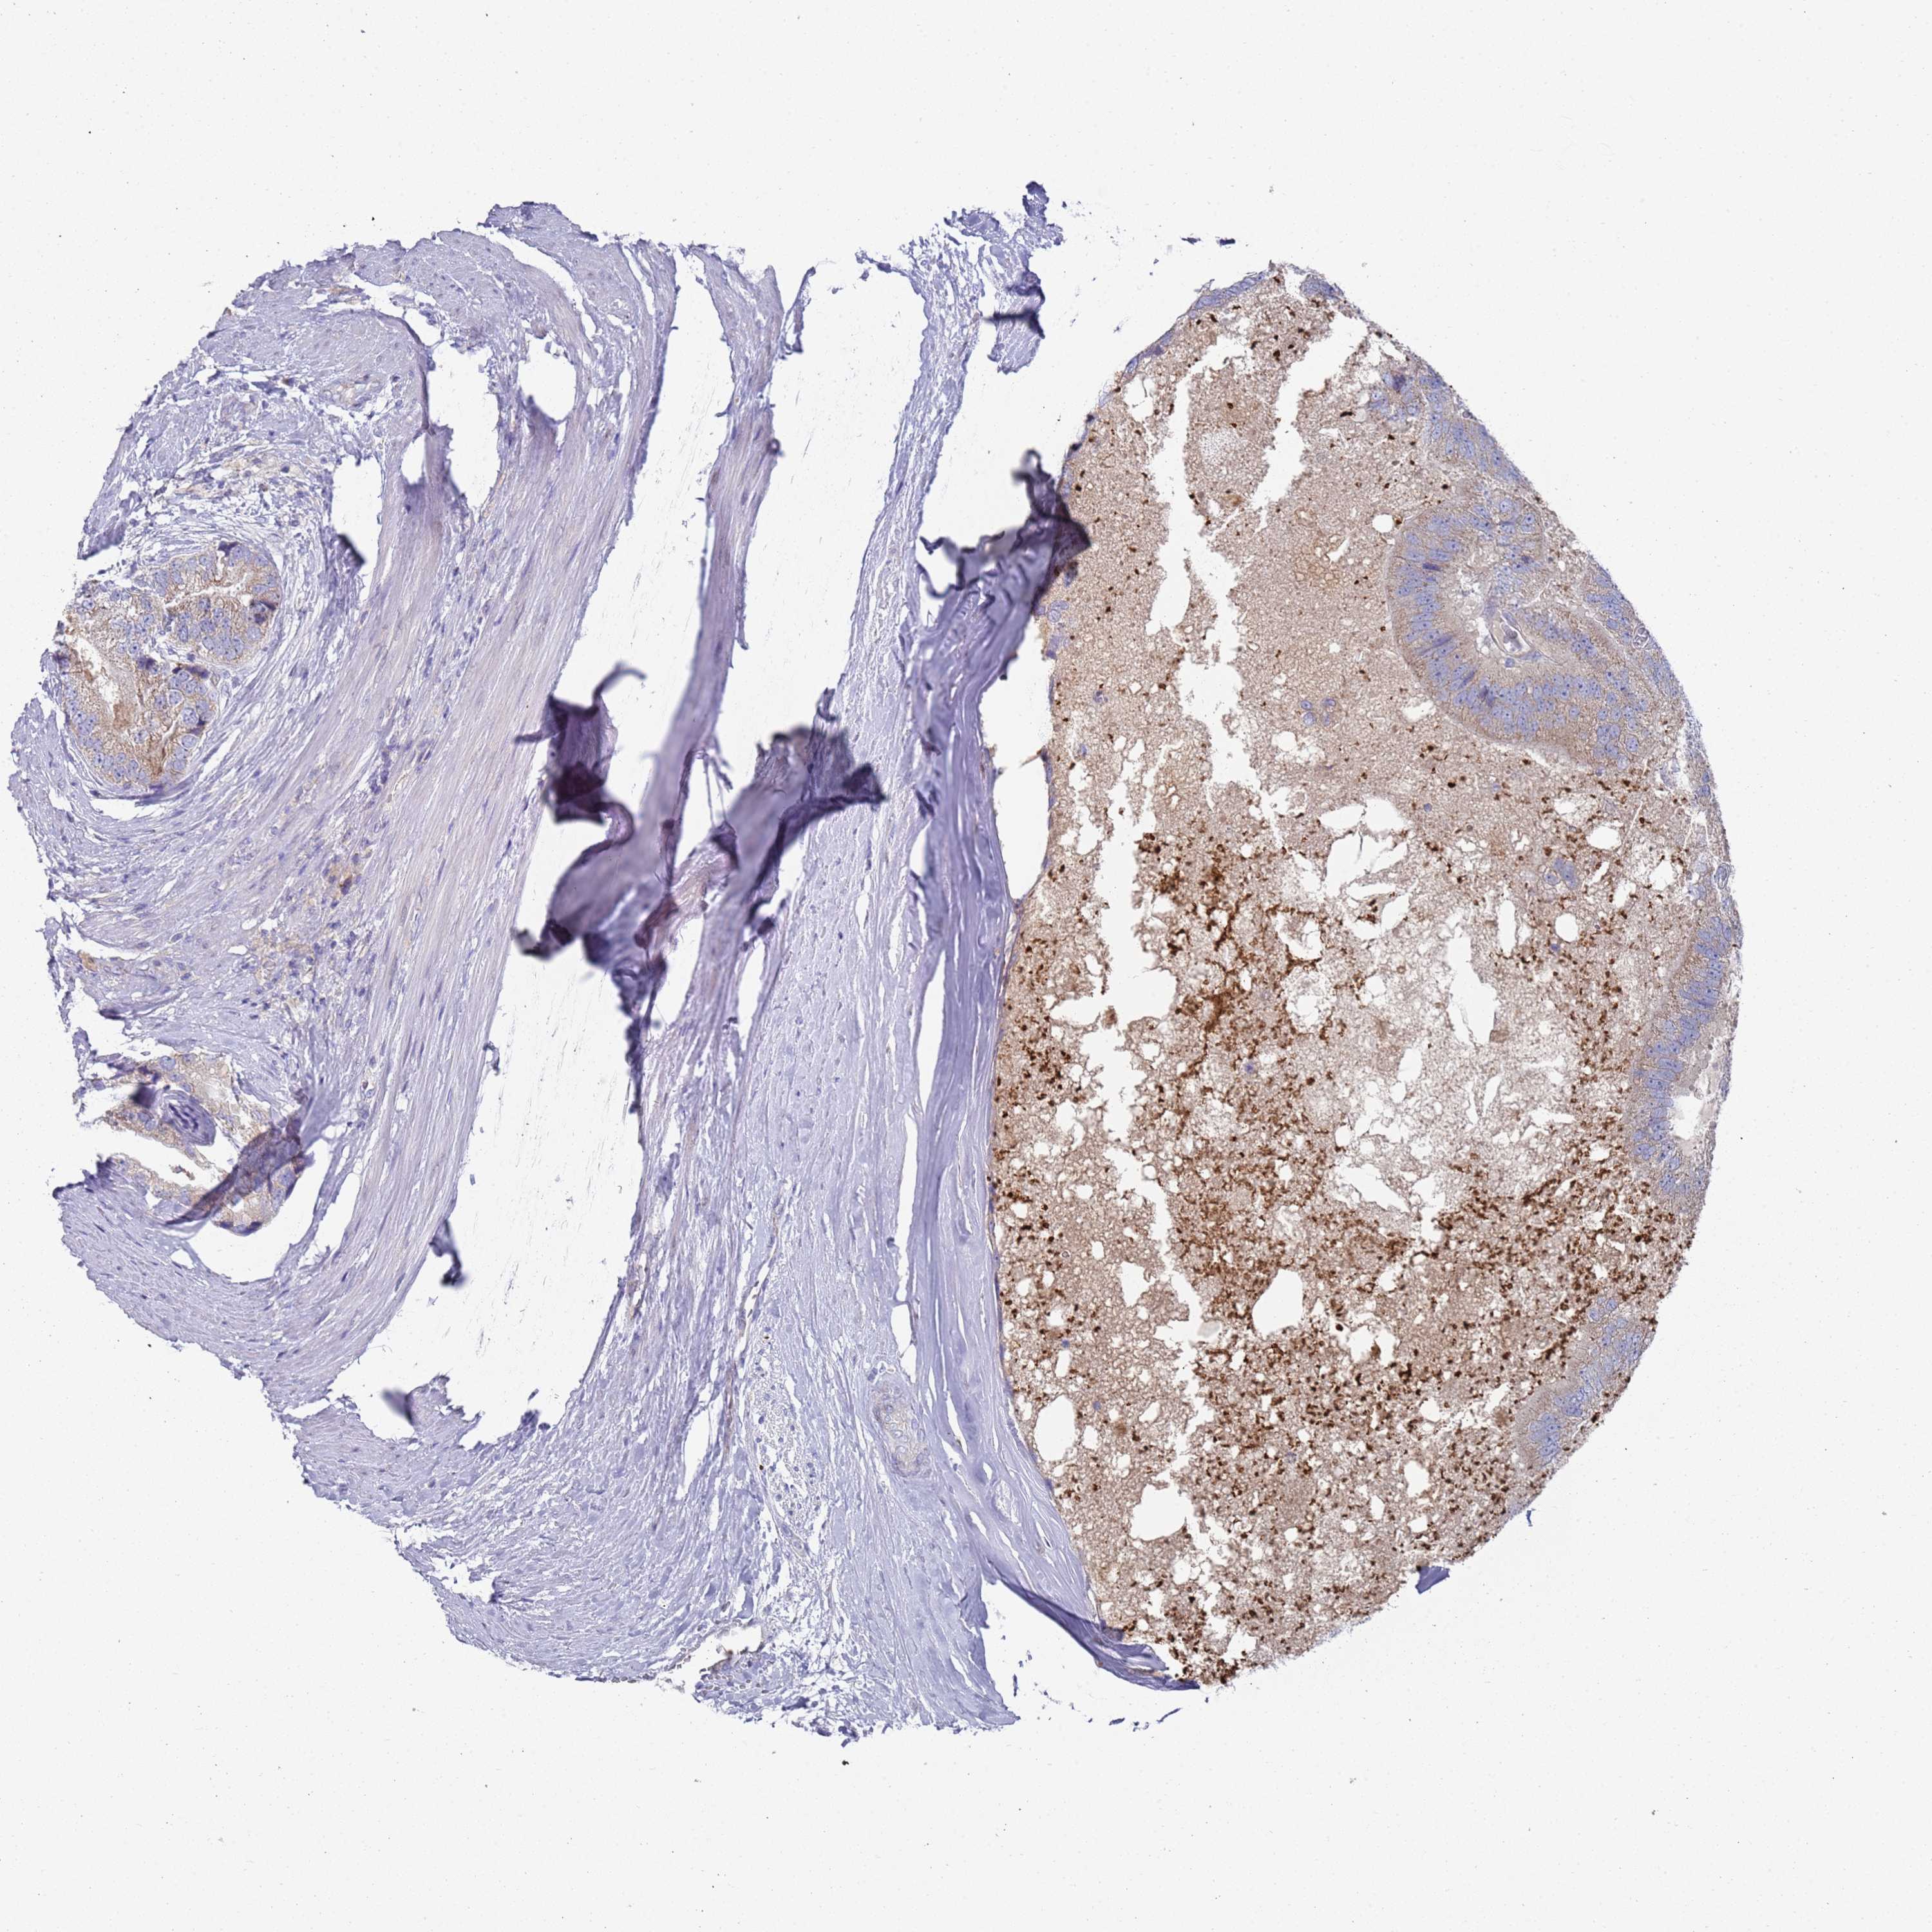

PROSTATE CANCER - Protein expressioni

A mouse-over function shows sample information and annotation data. Click on an image to view it in a full screen mode. Samples can be filtered based on level of antibody staining by selecting one or several of the following categories: high, medium, low and not detected. The assay and annotation is described here.

Note that samples used for immunohistochemistry by the Human Protein Atlas do not correspond to samples in the TCGA dataset.

Antibody stainingi

Antibody staining in the annotated cell types in the current human tissue is reported as not detected, low, medium, or high, based on conventional immunohistochemistry profiling in selected tissues. This score is based on the combination of the staining intensity and fraction of stained cells.

Each image is clickable and will lead to virtual microscopy that enables deeper exploration of all samples and also displays staining intensity scores, fraction scores and subcellular localization as well as patient and tissue information for each sample.

Antibody HPA021453

Antibody HPA045649

Staining

High

Medium

Low

Not detected

Intensity

Strong

Moderate

Weak

Negative

Quantity

>75%

75%-25%

<25%

None

Location

Nuclear

Cytoplasmic/membranous

Cytoplasmic/membranous,nuclear

Adenocarcinoma, NOS

Adenocarcinoma, High grade

Adenocarcinoma, Low grade